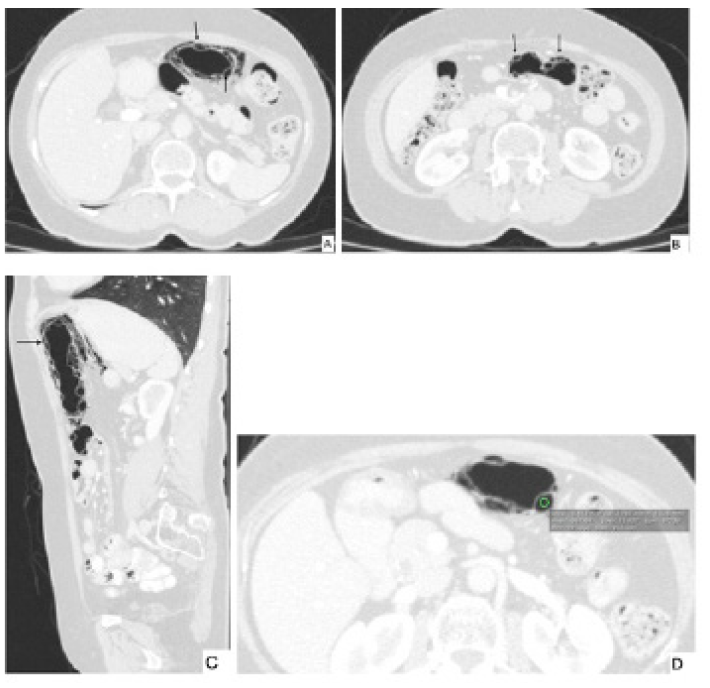

Se trataba de una mujer de 66 años sin antecedentes personales relevantes y quien consultó por un dolor abdominal difuso sin otros síntomas asociados. Al examen físico no se encontraron signos de irritación peritoneal. Se solicitó tomografía de abdomen contrastado en la que se identificaron múltiples imágenes hipodensas con unidades hounsfield (UH) promedio de -967, con morfología circular y lineal comprometiendo la pared del colon transverso (figura 2). No se observó aire en la vena porta, neumoperitoneo ni otras complicaciones. Se le realizó colonoscopia la cual no encontró anormalidades. La paciente fue manejada de forma expectante con mejoría de su cuadro clínico, por lo que se realizó el diagnóstico de neumatosis quística.

El patrón que más se ha asociado a enfermedad benigna es el patrón circular (quístico) 2,7,8, el cual es mas común en el colon y está descrito en neumatosis intestinal quística 2,9,14. Por el contrario, el patrón lineal fue descrito por Kernagis et al. cuando ocurre infarto transmural 2 (figura 3) y está relacionado en el tipo secundario 7. El patrón curvilíneo también se ha relacionado mas con formas severas 8.

Hay otros hallazgos en la tomografía que ayudan a hacer diagnóstico de enfermedades severas, tales como engrosamiento de la pared del asa intestinal, liquido libre o estriación de la grasa y tejido blando adyacente, entre otros 1,2. Si los espacios quísticos de la pared se distribuyen en un segmento intestinal que sigue un territorio vascular es probable que el origen sea una enfermedad severa 2. Un signo de isquemia intestinal es la presencia de gas en el sistema porta 9. Este hallazgo también puede estar presente en el contexto de trauma abdominal, colecistitis crónica, colangitis, pancreatitis y postoperatorio de trasplante hepático 9. En la tomografía se definen hipo densidades lineales ramificadas en la periferia del parénquima hepático 1.